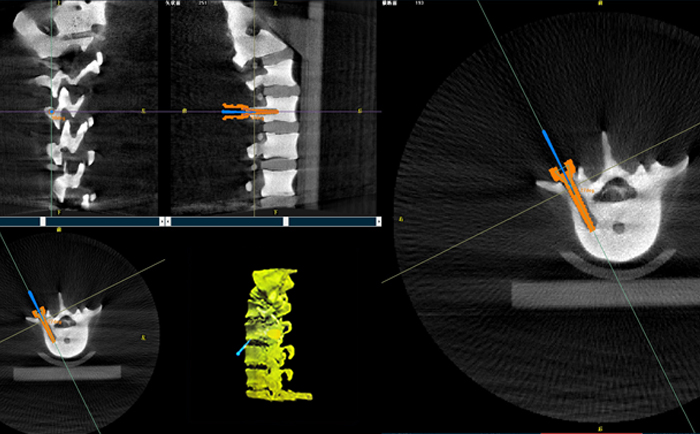

以椎弓根螺釘置入手術(shù)為例,傳統(tǒng)手術(shù)為了準(zhǔn)確定位,需要將其多次進(jìn)出反復(fù)選擇,增加了神經(jīng)損傷與螺釘損壞的風(fēng)險(xiǎn)。但外科手術(shù)機(jī)器人可通過術(shù)前規(guī)劃把手術(shù)入路、方向、釘子深度都規(guī)劃好,基本做到一步到位,讓手術(shù)更加安全。

手術(shù)開始前,外科手術(shù)機(jī)器人與3D C形臂對患者的患處進(jìn)行了一次掃描,做到“知己知彼”;接著電腦系統(tǒng)為每一顆螺釘設(shè)計(jì)出前進(jìn)的路徑;隨后,“穩(wěn)如泰山”的機(jī)器人之手——機(jī)械臂,開始為每條路徑掃除障礙,猶如鋪設(shè)火車軌道;最后沿標(biāo)準(zhǔn)路徑置入螺釘,猶如火車行駛在車軌之上,最終準(zhǔn)確置入螺釘。

普愛醫(yī)療的外科手術(shù)機(jī)器人經(jīng)國家藥監(jiān)局批準(zhǔn),作為第三類醫(yī)療器械開始上市并應(yīng)用于臨床,主要用于椎弓根螺釘內(nèi)固定術(shù)、經(jīng)皮穿刺椎體成形術(shù)等術(shù)式(包括頸椎、腰椎、胸椎等)等脊柱外科手術(shù)。輔助準(zhǔn)確定位植入物或手術(shù)器械,精度達(dá)到亞毫米級,尤其對微創(chuàng)手術(shù)、高風(fēng)險(xiǎn)手術(shù)具有明顯優(yōu)勢,可有效降低手術(shù)風(fēng)險(xiǎn)、減少手術(shù)并發(fā)癥。